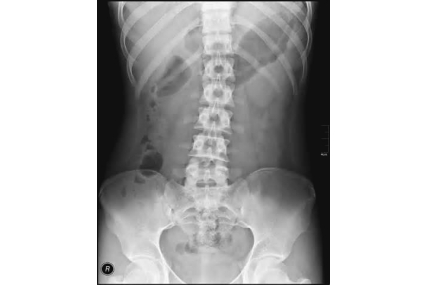

我患有腰背痛,應否去照X-光?

大部份機械性腰背痛(Mechanical back pain) 都不能從X-光片中找出問題的原因及位置,而X-光片也可能不會影響我們的治療。但是,如果你經過治療後也沒有果效或有一些可疑的情況,X-光可以幫助醫生及物理治療師找出一些隱藏的疾病。所以當有腰背問題時,都應找專業醫護人員作出正確的檢查。

我的腰部X光片有骨刺,是否會令我坐久後會痛?生骨刺是否很痛?做物理治療有用嗎? 骨刺會否消失? 請問有何治療方法?

如果閣下的腰部X光片有骨刺(即是腰椎骨邊沿的骨質增生),代表你的腰部有退化現象。骨刺是由於腰椎局部長期受壓(如坐姿不正確、偏向一側、過重、長期彎腰等),令身體意識到此部位壓力大,而增生更多的骨質來分擔壓力。其實骨刺的成分與正常的骨骼是同樣成份,只是生長在不正確的位置。

骨刺本身不會痛,故有些人身體內有骨刺,但完全沒有痛楚感覺。由於骨刺令四周的空間減少,壓迫著其他軟組織(筋腱、肌肉、神經線)或關節,阻礙關節活動及引起發炎,便會產生痛的感覺。已生長的骨刺不會因藥物或其他治療而消失,目前只有手術可直接切除骨刺,但如沒有處理令骨刺形成的壓力因素,骨刺很大機會再生。如沒有正視骨刺問題,骨刺可能會繼續生長,越來越大,造成更大的阻礙及炎症。反之,當發現骨刺後,糾正錯誤的姿態或動作,減低骨刺部份再受壓,才是治本的方法。

物理治療師經過詳細的臨床檢查及評估後,會作出相應的治療,籍此減低因骨刺引起的痛楚,降低神經線受壓、減少麻痹及痛楚、增加關節活動幅度及預防骨刺再增生。物理治療方法包括:電療、超聲波、手法治療、牽引、姿勢糾正及針對性運動治療。